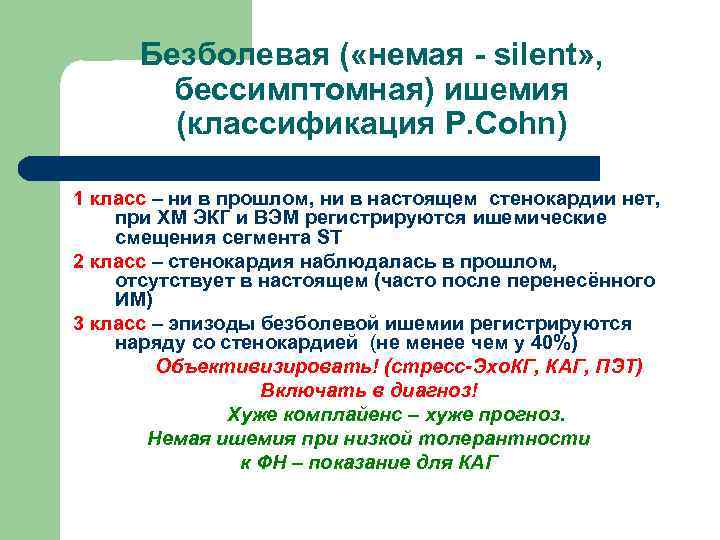

Безболевая ( «немая - silent» , бессимптомная) ишемия (классификация P. Cohn) 1 класс – ни в прошлом, ни в настоящем стенокардии нет, при ХМ ЭКГ и ВЭМ регистрируются ишемические смещения сегмента ST 2 класс – стенокардия наблюдалась в прошлом, отсутствует в настоящем (часто после перенесённого ИМ) 3 класс – эпизоды безболевой ишемии регистрируются наряду со стенокардией (не менее чем у 40%) Объективизировать! (стресс-Эхо. КГ, КАГ, ПЭТ) Включать в диагноз! Хуже комплайенс – хуже прогноз. Немая ишемия при низкой толерантности к ФН – показание для КАГ